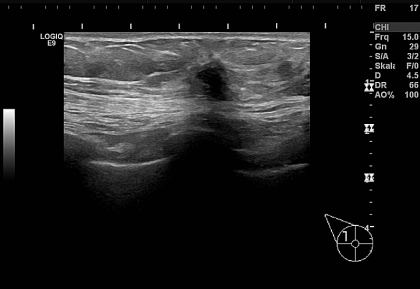

Die Biopsienadel wird durch einen Hochgeschwindigkeitsstanzapparat geführt, der aus dem Tumor eine Gewebsprobe (Stanzzylinder) entnimmt und nach der Gewebsstanze noch im Tumor liegt. Dadurch kann man nachzuweisen, dass die Gewebsprobe - wie in diesem Fall - tatsächlich aus dem Zentrum des Tumors entnommen worden ist.

Die Untersuchung des Knotens hat ein kleines Mammacarcinom ergeben. Die Patientin konnte brusterhaltend operiert werden.